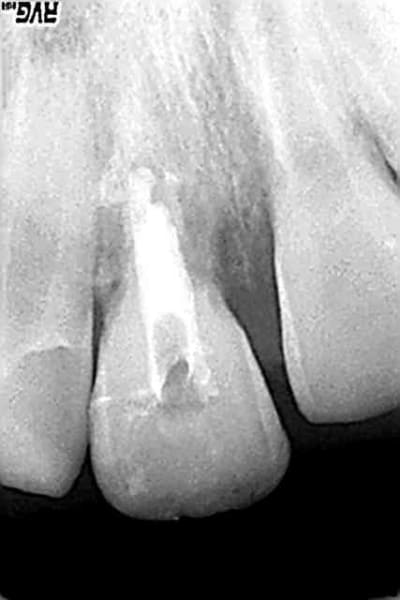

de la 11 obturée aujourd'hui au MTA

compte tenu de la longueur et de la dilacération de la racine ,le but est de reculer l'échéance de la perte de cette dent...,puis ce sera 11 collée sur arc palatin ou bridge collé mais j'aime pas:):),puis implant

21 et 22 sous surveillance

> de la 11 obturée aujourd'hui au MTA

> compte tenu de la longueur et de la dilacération

> de la racine ,le but est de reculer l'échéance de

> la perte de cette dent...,puis ce sera 11 collée

> sur arc palatin ou bridge collé mais j'aime

> pas:):),puis implant